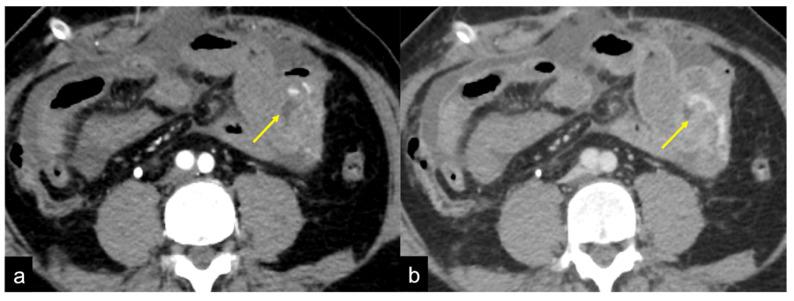

CT 血管造影在急性胃肠道出血中的作用:活跃和隐匿性发现的影像学描述。

The Role of CT-Angiography in the Acute Gastrointestinal Bleeding: A Pictorial Essay of Active and Obscure Findings.

Gastrointestinal bleeding is a potentially life-threatening abdominal emergency that remains a common cause of hospitalisation. Although 80-85% of cases of gastrointestinal bleeding resolve spontaneously, it can result in massive haemorrhage and death. The presentation of gastrointestinal bleeding can range from asymptomatic or mildly ill patients requiring only conservative treatments to severely ill patients requiring immediate intervention. Identifying the source of the bleeding can be difficult due to the wide range of potential causes, the length of the gastrointestinal tract and the intermittent nature of the bleeding. The diagnostic and therapeutic approach is fully dependent on the nature of the bleeding and the patient's haemodynamic status. Radiologists should be aware of the appropriate uses of computed tomography angiography and other imaging modalities in patients with acute gastrointestinal bleeding, as well as the semiotics of bleeding and diagnostic pitfalls in order to appropriately diagnose and manage these patients. The learning objective of this review is to illustrate the computed tomography angiography technique, including the potential role of dual-energy computed tomography angiography, also highlighting the tips and tricks to identify the most common and uncommon features of acute gastrointestinal bleeding and its obscure form.

胃肠道出血是一种潜在的危及生命的腹部急症,仍然是导致住院的常见原因。尽管 80-85%的胃肠道出血病例会自发缓解,但它可能导致大量出血和死亡。胃肠道出血的表现范围从无症状或轻度不适的患者仅需保守治疗到需要立即干预的严重疾病患者。由于潜在原因广泛、胃肠道长度长以及出血间歇性,确定出血部位可能很困难。诊断和治疗方法完全取决于出血的性质和患者的血流动力学状态。放射科医生应该了解在急性胃肠道出血患者中使用计算机断层血管造影和其他成像方式的适当用途,以及出血的征象和诊断陷阱,以便对这些患者进行适当的诊断和治疗。本次综述的学习目标是说明计算机断层血管造影技术,包括双能计算机断层血管造影的潜在作用,还强调了识别急性胃肠道出血及其隐匿形式的最常见和不常见特征的技巧和窍门。